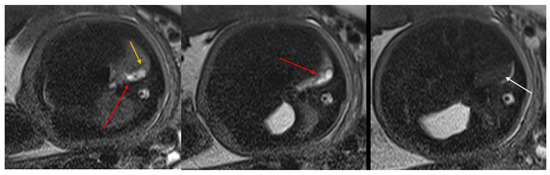

Figure 2. CPAM type II. Axial HASTE T2 MR images show a hyperintense lesion characterized by at least six cystic images (red arrow) of 2–6 mm at the lung base, with extension to the right posterior lung (orange arrow). No compression on the diaphragm or mediastinum. Minimal pleural effusion layer (white arrow).